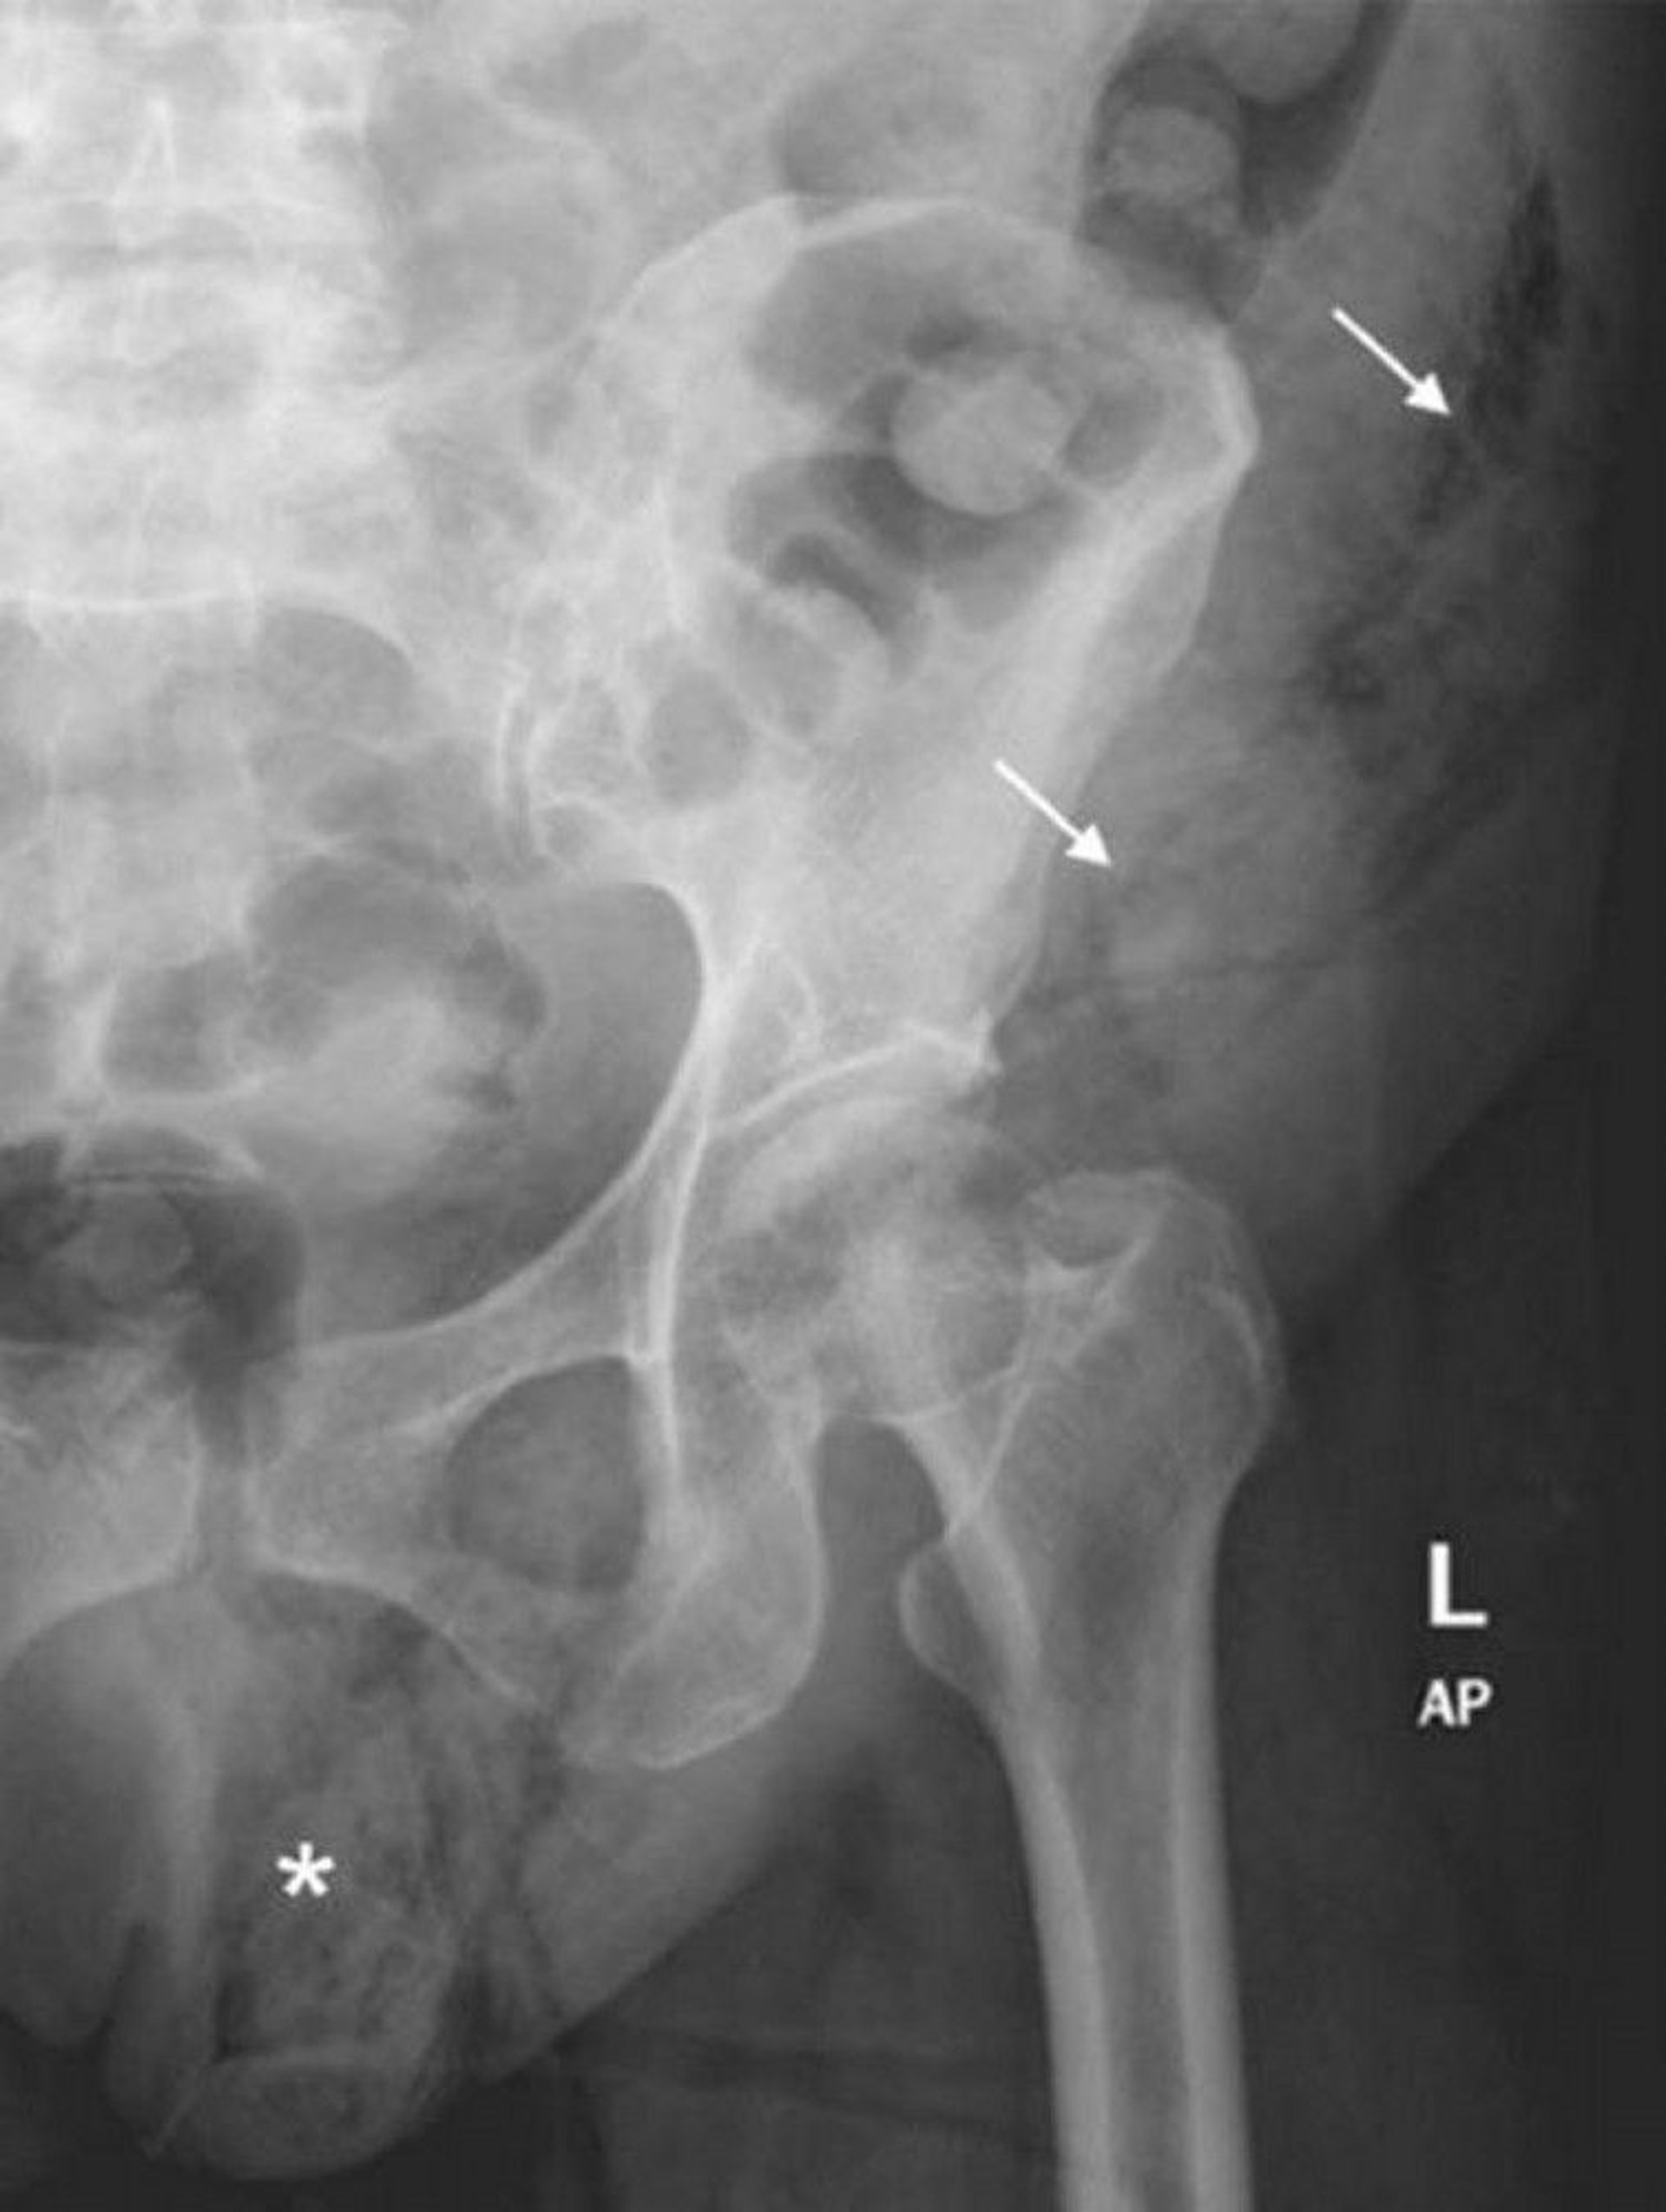

Fournier Gangrene (Abdominal X-Ray)

This abdominal x-ray shows an extension of soft-tissue gas from the left hemiscrotum (*) to the left abdominal wall (arrows).